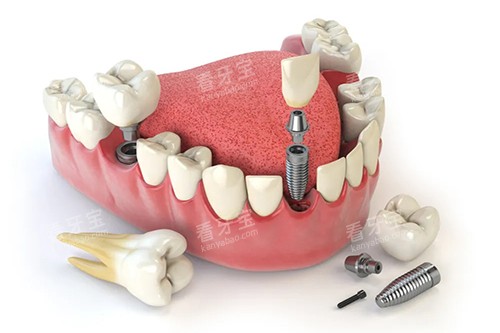

在种植牙领域,德瓦口腔的医生们更是有着不错的表现。

他们掌握了较高的种植牙技术,能够精密地植入种植体,提高种植牙的可行性和稳定性。

同时,医生们会充分考虑患者的口腔健康状况和经济实力,为患者推荐合适的种植体品牌和型号,让患者既能拥有健康的牙齿,又能在经济上得到合理的安排。